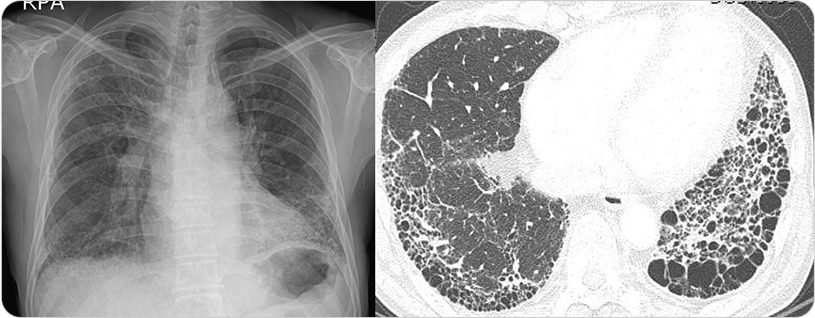

그림 : 간질성 폐질환 중 폐섬유화증을 보이는 흉부X선과 흉부전산화단층촬영(CT) 결과

이 질환은 광범위 사이질 폐질환(Diffuse Parenchymal Lung Disease), 미만성 간질성 폐질환(Diffuse Interstitial Lung Disease)라고도 불렸습니다. 그래서 간질성 폐질환(ILD)은 폐 간질부(interstitial compartment)의 증식과 함께 다양한 염증 세포들의 침윤, 그리고 때로는 섬유화(fibrosis)가 동반되는 질환을 통틀어서 말합니다. 간질성 폐질환(ILD)의 진단을 위해서 흉부전산화단층촬영(CT) 후 임상 소견, 그리고 폐 조직검사 등을 종합한 접근이 필요합니다.